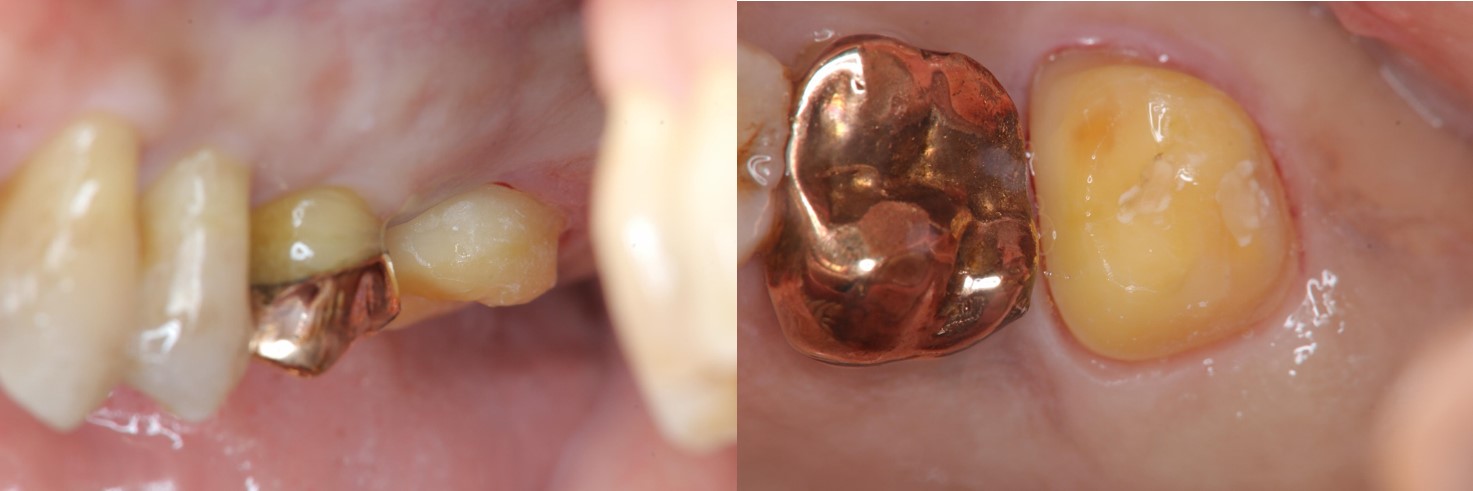

全瓷冠牙齒製備

全鋯冠